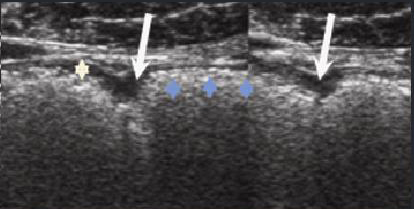

En generalement la paroi digestive

normale se presente en 3 couche : la sereuse , la

musculeuse , la sous muqueuse et la muqueuse . A interface

de muqueuse est la lumiere du tube digestif . A interface de

la sereuse est la graisse peri digestive . Tout se formaient

en 5 couche alternativement de hypo a hyperechogene :

| |

| - Interface interne : Hyperechogene

|

| - La muqueuse

: ,Hypoechogene |

| - La sous musqueuse

: Hyperechogene

| -La couche musculeuse : Hypoechogene |

| -Interface sereuse -graisse

peridigestive : hyperechogene |

Il y a la difference de image

echographique intestin -grele et la colon :

L'epaisseur de la paroi de l'intestin normalement est en

moyen a 3mm avec des plies muqueuses et de peristaltisme

marquee , mais epaisseur du colon varie entre 5mm et en

moindre de mouvement peristaltisme . Au colon droit : les

haustras son tres espace et colon gauche , les haustration

sont plus nombreuse . Au ileon la

hauteur des plies muquese est diminue et espace entre des

plies muqueuse sont augementes

Colon : L'epaisseur du colon varie

entre 5mm et peristaltisme presque interceptible .

Colon droit : Les haustrations

sont plus espacees et la paroi anterieure presque

toujours aerique ** |

Colon gauche : Haustration sont plus nombreuse s avec hypertrophie

musculeuse |